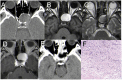

Results: Among the eight cases, the lesions were identified as follows: Solitary fibrous tumor (SFT) in one case, Lymphocytic hypophysitis (LYH) in one case, Cavernous sinus hemangiomas (CSH) in one case, Ossifying fibroma (OF) in two cases; Sphenoid sinus mucocele (SSM) in one case, Pituitary abscess (PA) in two cases. All patients underwent successful EETS, and their diagnoses were confirmed through pathological examination. Postoperatively, all patients had uneventful recoveries without occurrences of diabetes insipidus or visual impairment.